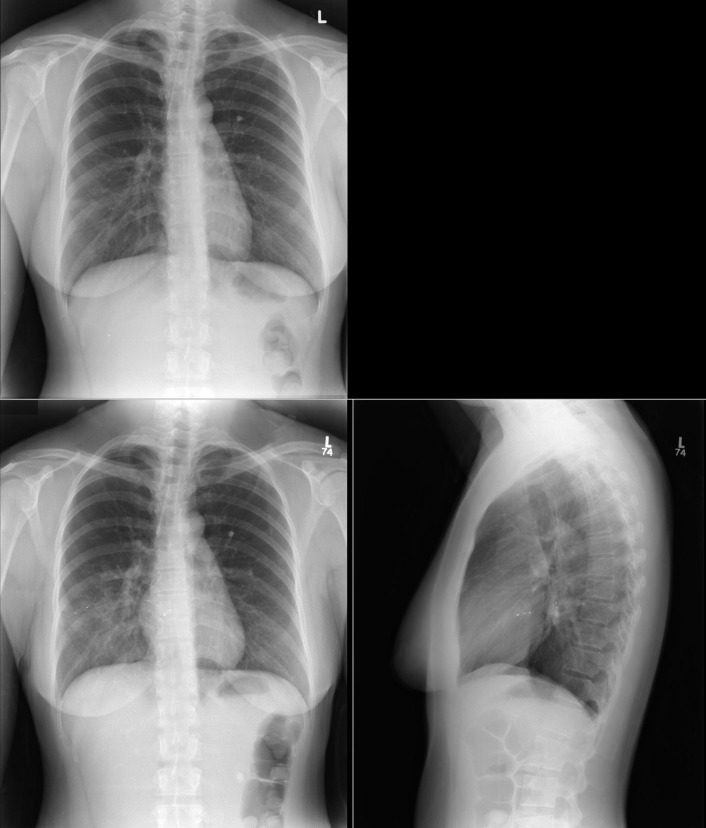

A patent foramen ovale is present in 25% to 30% of the adult population ( Figs. 18-1 to 18-4 ). Any magnitude of shunting across it in normal circumstances is undetectable radiographically. Percutaneous patent foramen ovale closure devices are fairly commonly inserted and are radiographically evident.

See Figures 18-5 to 18-31 . Possible findings are discussed in the following sections.